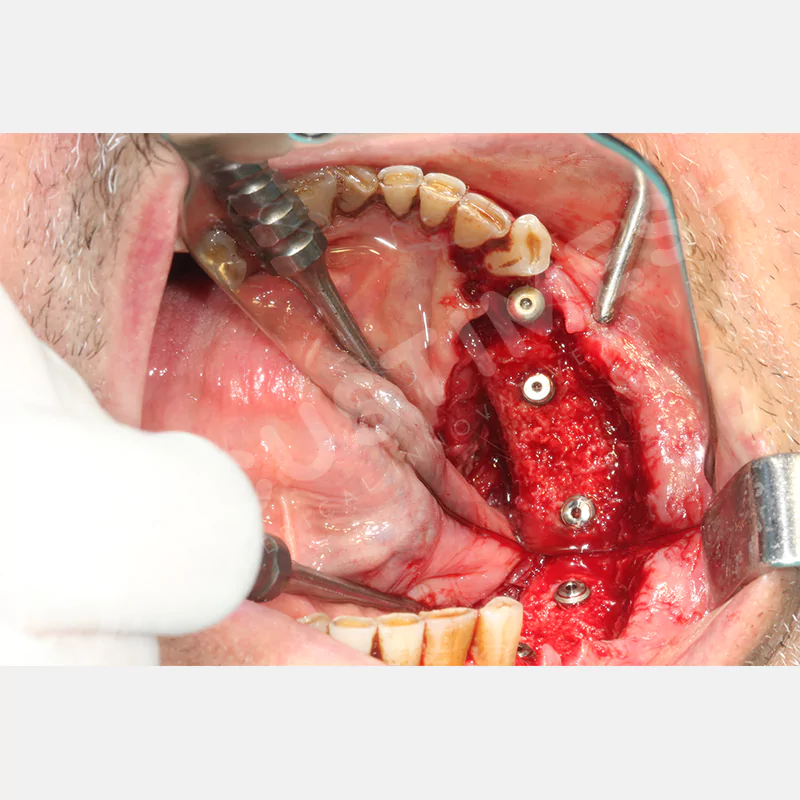

Dental implant uygulanamayan hastalarda kemik rejenerasyonunu sağlamak üzere geliştirilen kişiye özel titanyum mesh, kemik augmentasyon işlemlerinde greft materyalinin korunması ve yeni kemik oluşumunun desteklenmesi amacıyla kullanılan, hastanın kendi anatomisine tam uyumlu titanyum bir bariyer sistemidir.

Medikal sınıf titanyumdan, hastanın bilgisayarlı tomografi verileri kullanılarak CAD yazılımlarıyla tasarlanan ve 3D baskı teknolojisiyle üretilen bu yenilikçi çözüm, özellikle kompleks kemik defektlerinde standart meshlerin sağlayamadığı üstün mekanik stabilite ve mükemmel adaptasyon özellikleri sunar. Anatomik yapıya tam uyum sağlayarak greft materyalinin yerinde kalmasını garanti ederken, optimal vaskülerizasyonu destekleyerek kemik rejenerasyon sürecini hızlandırır.

- Cerrahi Süre Kısalması

- Düşük Komplikasyon Riski